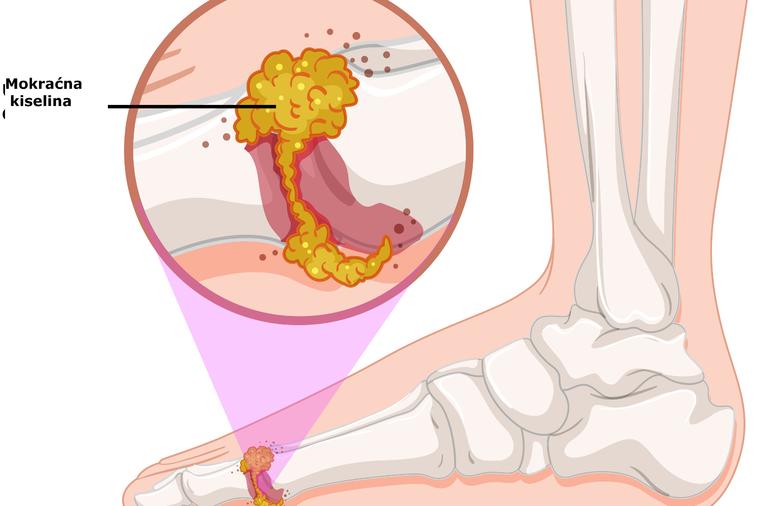

Giht je inflamatorni oblik artritisa koji dolazi na paroksizmalni oblik u obliku crvenila, oticanja zglobova i bolova. Ponekad je čak i vrlo bolno kretanje, oseća se ukočenost i otok tela. Čest uzrok gihta je višak mokraćne kiseline u organizmu.

Kada bubrezi ne rade dobro svoj posao i ne mogu da uklone svu mokraćnu kiselinu iz organizma, ona se kristalizujme i taloži oko zglobova. To dovodi do početka upalnog procesa.Kako ukloniti mokraćnu kiselinu iz tela?